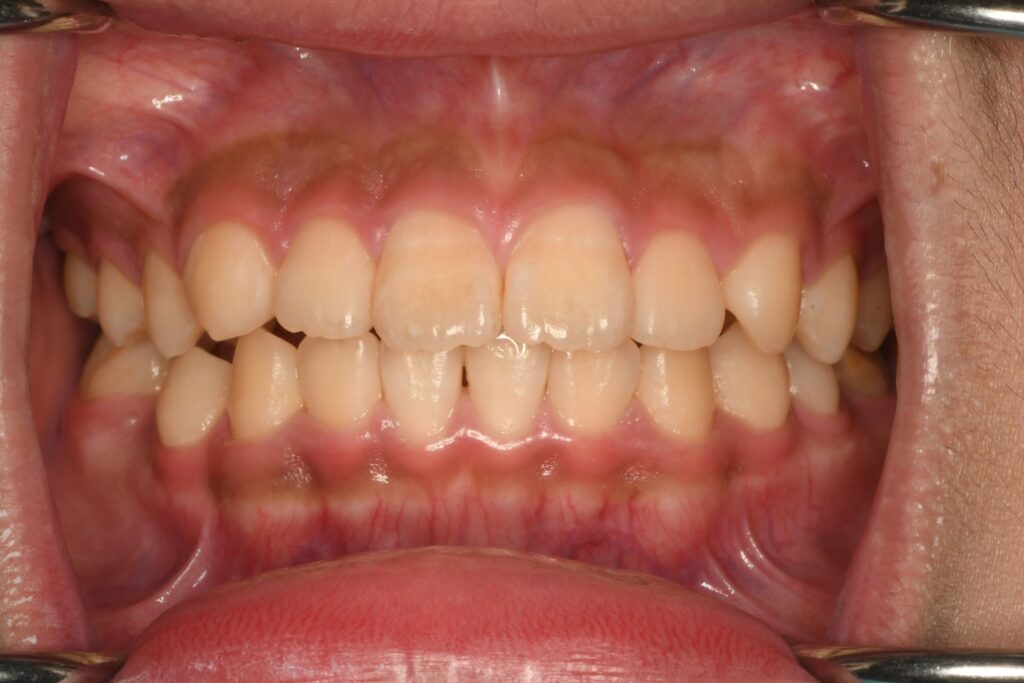

正面から観るとわかりずらいと思いますが、噛み合わせが微妙にズレています。ズレている理由は、歯が1本もともと無いからです。いわゆる先天欠損です。以前から把握できていましたが、色々と相談をしながらどうしようかを考えていました。最初は子供はをできる限り使っていこう‼︎という計画でいましたが、あまり持ちませんでした。歯がなくなっても本人がそれほど気になっていなかったこともあり、歯が無い状態で過ごしつつ、歯の病気にさせないように関わり続けていました。歯を削ったり、インプラントにしたりするのは、できる限りおすすめしたくなかったので矯正治療の提案をしていました。

今回の計画は、数段階に分けて治療をしていきます。1段階目は歯の位置関係をできるだけ整える。2段階目は先天欠損している部位の隙間をなくす。3段階目は全体的にはの位置を整える。ことにしました。結構時間がかかると思いますが、本人もお母さんも同意してくれたので治療を開始することになりました。